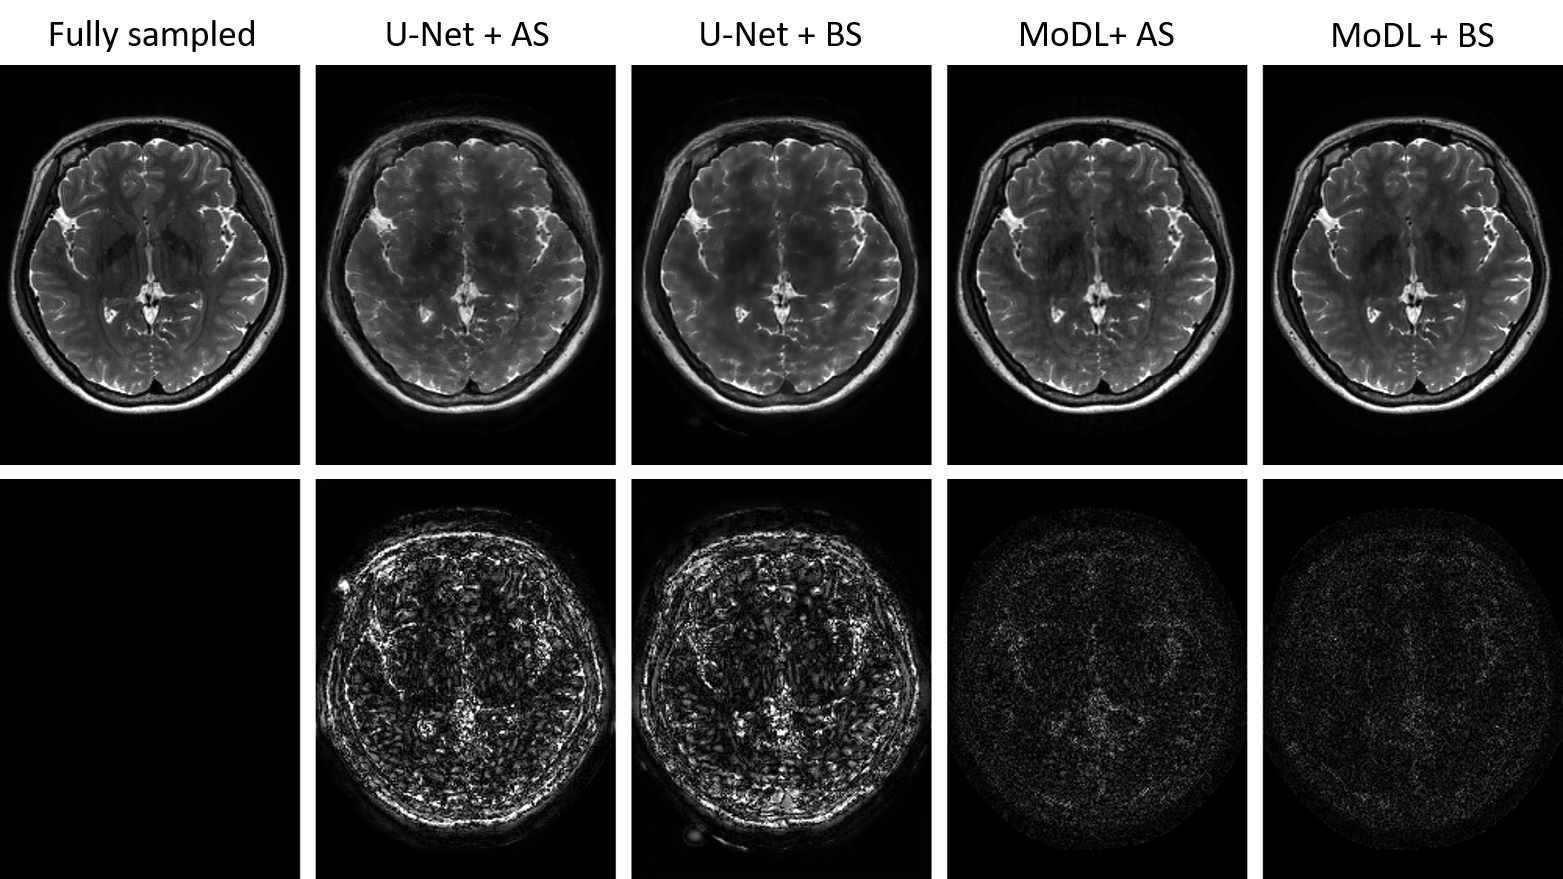

Figure 2: Reconstruction results on one test slice by four combinations of reconstruction network and sampling pattern optimization network with 10% under-sampling ratio. First row: reconstruction results; second row: 5×5\times absolute error maps (window level: [0, 0.5]). MoDL + BS equipped with ST estimator had the best performance.

Fig. 2 shows the reconstruction results from one of the test subjects to demonstrate the performance improvement of the extended LOUPE over vanilla LOUPE. Four combinations of reconstruction network and sampling pattern optimization network were tested and compared. Binary sampling patterns were generated during test phase. From Fig. 2, MoDL provided better reconstruction results compared to U-Net, while for both U-Net and MoDL reconstruction networks, BS (binary sampling) gave less noisy reconstructions than AS (approximate sampling) during test phase. Quantitative comparisons in terms of PSNR (peak signal-to-noise ratio) and SSIM (structural similarity index measure [29]) are shown in Table 1, where MoDL + BS had the best performance.